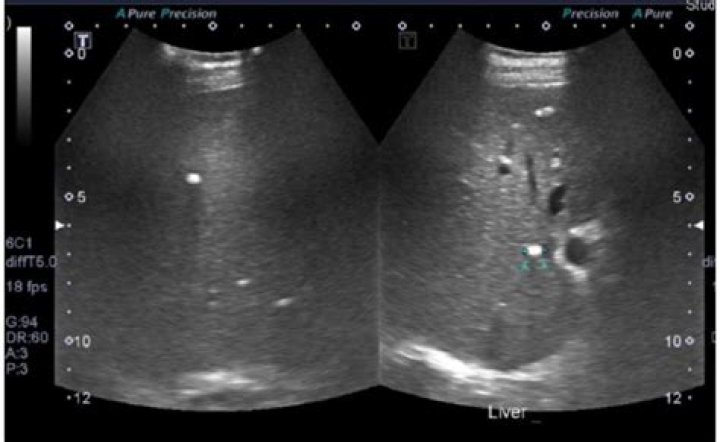

What causes calcification on the liver?

The main causes of hepatic calcification are infections-e.g. tuberculosis, histoplasmosis, brucellosis, schistosomiasis, hydatid cyst, cytomegalovirus, toxoplasmosis, Pneumocystis carinii infection, chronic amebic or pyogenic abscess, and chronic granulomatous disease of childhood.

Although relatively uncommon in daily clinical practice, calcification may be found in inflammatory hepatic lesions and in benign and malignant liver neoplasms. In hepatocellular adenoma, calcifications may be solitary or multiple and are usually located eccentrically within a complex heterogeneous mass.

Although relatively uncommon in daily clinical practice, calcification may be found in inflammatory hepatic lesions and in benign and malignant liver neoplasms. The most common source of calcified hepatic lesions is inflammatory conditions such as granulomatous diseases (e.g., tuberculosis).